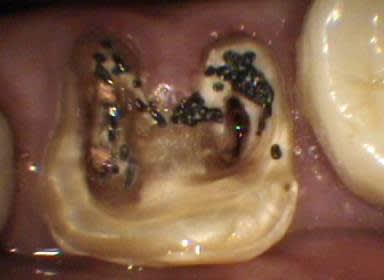

Voici un cas moins gentil avec élimination de la cause du problème pour reprendre les termes de Marc.

Il s'agit d'une patiente de 90 ans sur qui je reconstituais les secteurs postérieurs mandibulaires, ce qui fera l'objet d'un prochain post d'ailleurs, et dont un simple détartrage révélait la présence d'une énorme carie sous le pilier distal d'un bridge reliant la 23 à la 26.

Ayant intérêt à éviter de commencer un gros chantier alors qu'un autre était en cours, j'ai opté pour dégager et éliminer cette carie en conservant provisoirement ce bridge qui tenait bien, avant de traiter ce secteur en tachant de récupérer la racine de la 26 si possible.